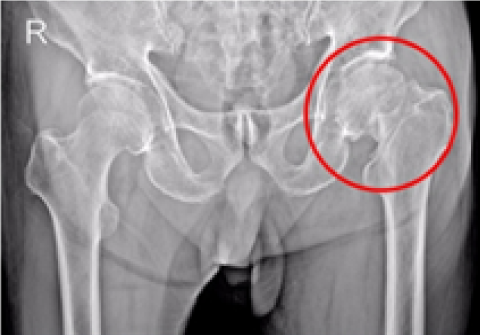

무릎 인공관절 부분치환술

2016.06.27

2016.12.28